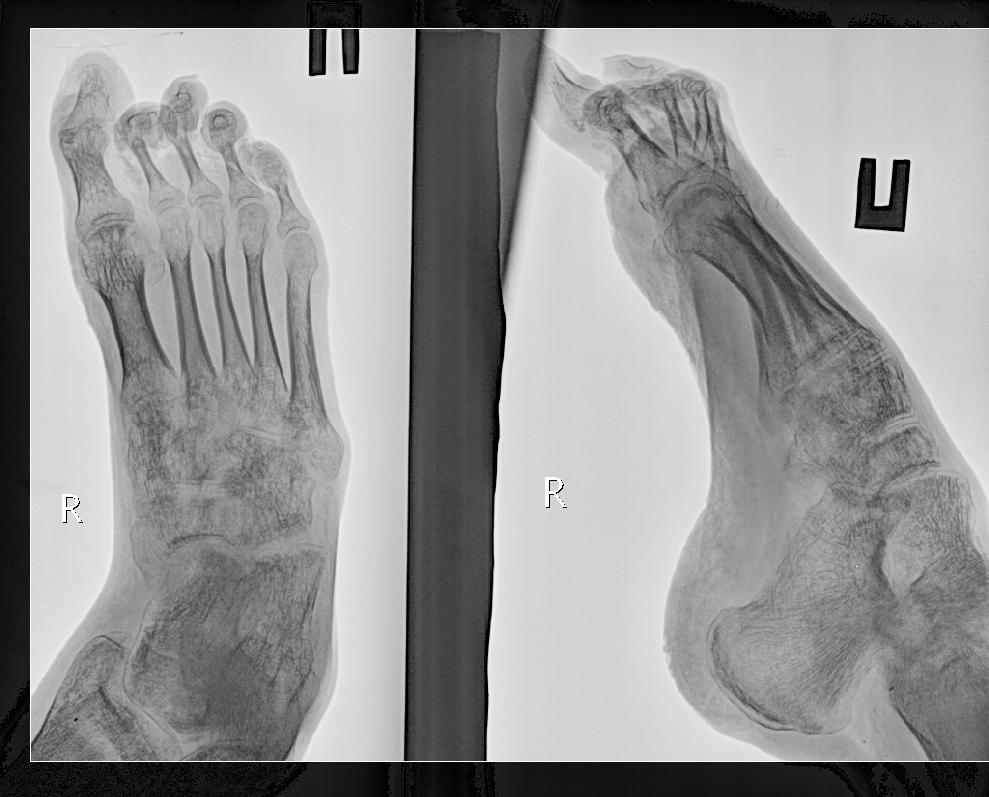

[Ortho] Деформация стопы

Добавляю фото и рентгенограммы.